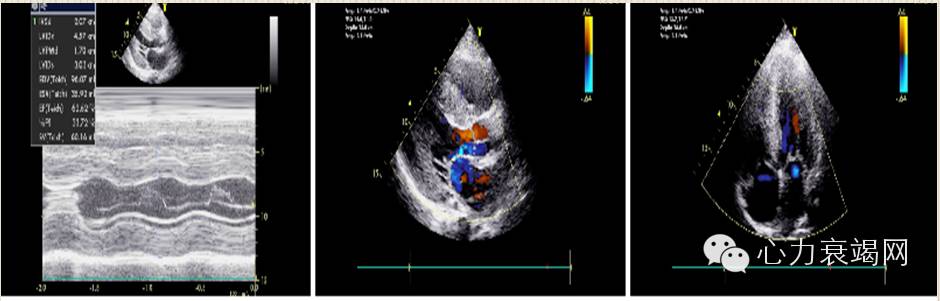

心脏超声:左房轻度增大,余房室内径正常范围。室间隔与左室壁各阶段普遍均匀性增厚,室壁回声粗糙,呈斑点样改变,心肌纹理排列紊乱。室间隔及左室壁运动幅度及收缩期增厚率尚可。左室流出道未见狭窄。二尖瓣未见SAM现象,各瓣膜形态、结构及活动未见明显异常。心包腔未见异常。 多普勒检查:左室流出道血流速度正常,无明显压差。 二尖瓣口探及微量返流。

超声诊断:左房轻大,左室壁均匀肥厚,考虑非梗阻性肥厚型心肌病(对称性),左室舒张功能减低,左室收缩功能基本正常

3﹒超声心动图

超声心动图表现室壁增厚,心室腔变小,心房扩大以及左室功能不全征象。心包积液也很常见,但很罕见引起心包压塞。部分患者在增厚的心壁内可见闪烁的颗粒状结构,可能是因为含有淀粉和胶原体所致。